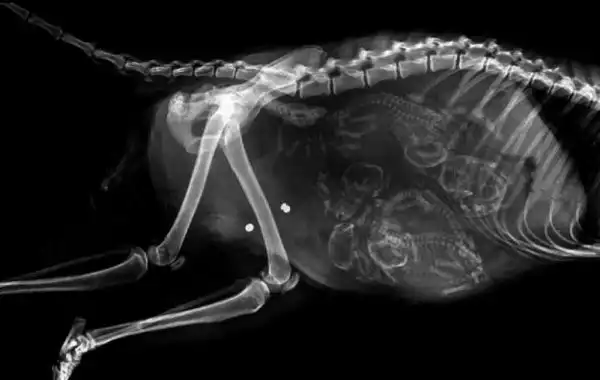

Еще одна беременная котейка